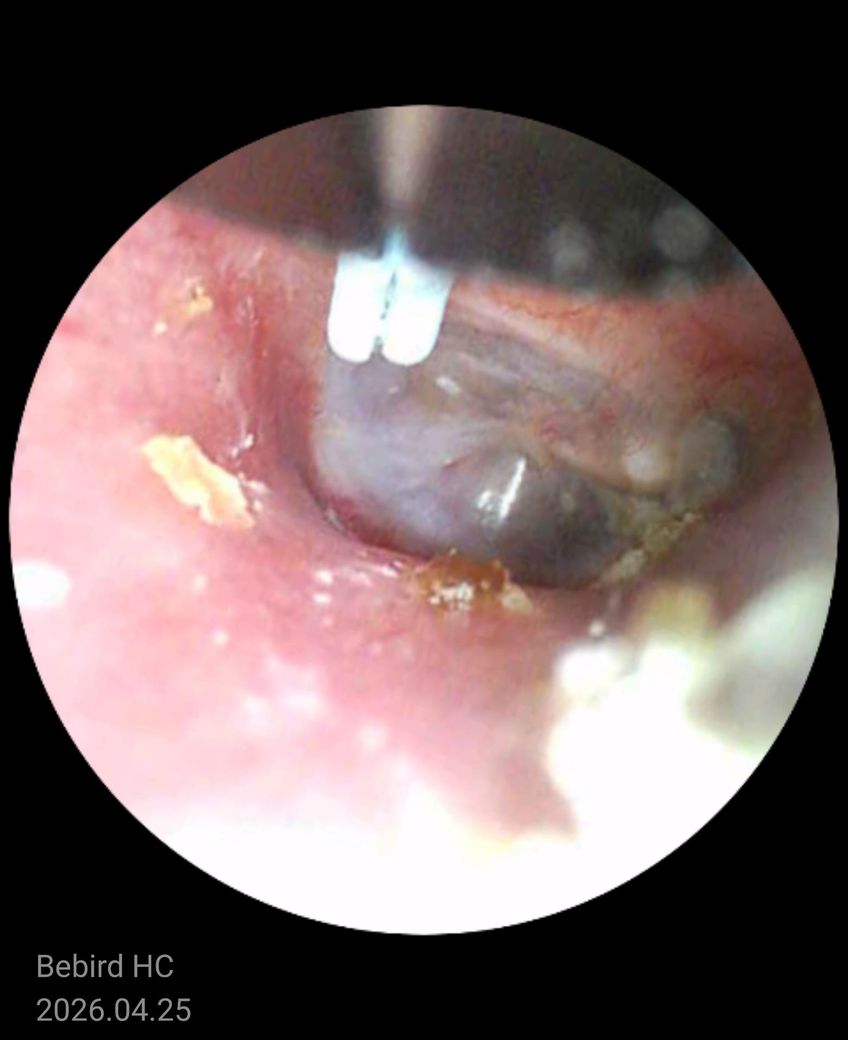

사진상 고막은 회색빛으로 유지되어 있고 뚜렷한 천공이나 심한 발적, 삼출(고름)이 차 있는 전형적인 중이염 소견은 보이지 않습니다. 대신 외이도 피부가 자극된 흔적과 이물(귀지, 각질)이 일부 보이며, 가려움·간헐적 통증·먹먹함이라는 증상 조합은 외이도염 또는 외이도 피부염 양상에 더 가깝습니다.

병태생리적으로는 귀를 자주 만지거나 이어폰 사용, 세정 과다 등으로 외이도 피부 장벽이 손상되면 가려움이 먼저 생기고, 2차로 염증이 생기면서 통증이나 먹먹함이 동반될 수 있습니다. 귀지와 각질이 고막 근처에 붙어 있으면 일시적인 이명이나 막힌 느낌도 유발할 수 있습니다.

중이염이라면 보통 지속적인 통증, 청력 저하, 발열 또는 고막 뒤 액체가 보이는 소견이 동반되는 경우가 많습니다. 현재 사진과 증상만으로는 가능성이 낮은 편입니다.

정리하면, 현재는 중이염보다는 외이도 피부 자극 또는 외이도염 가능성이 높고, 자극을 줄이고 필요 시 점이약 치료로 호전되는 경우가 많습니다.